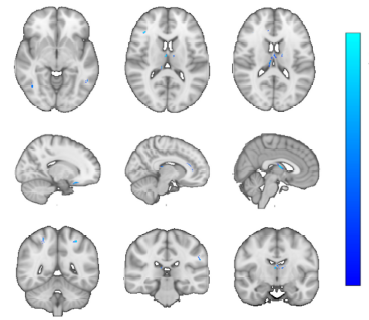

运动训练促进增强缺血性脑卒中后白质修复

Yating Mu, Xiaofeng Yang, Yifeng Feng, Liying Zhang, Jinghui Xu, Mingyue Li, Rui Wu, Shiying Li, Xiaofei He, Zejie Zuo, Xiquan Hu. Physical exercise promotes white matter repair after ischemic stroke[J]. Neural Regeneration Research, 2026, 21(6): 2397-2406.  doi: 10.4103/NRR.NRR-D-24-00861